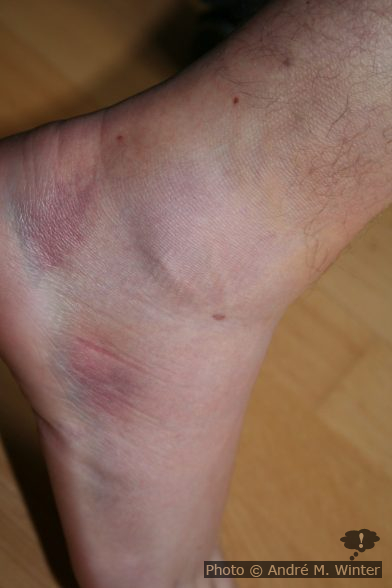

2006, ich war da 34 Jahre alt, hatte ich Bänderrisse/Bänderdehungen in der Ferse rechts aussen, die konservativ behandelt wurden. Diese Bänder sind nach wie vor nicht sehr fest, das heisst, ich knicke trotzdem immer wieder um. Ab diesem Zeitpunkt ging ich nur mehr ausschliesslich mit festen Bergschuhen ins Gelände und sonst habe ich immer feste Trekkingschuhe an. Die Fussmuskulatur verkümmert dabei zusehends.